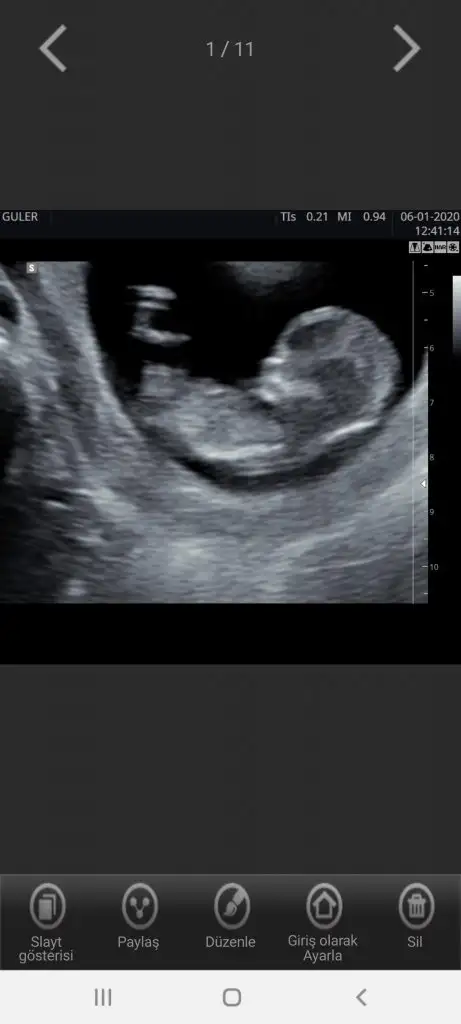

Keseye göre karından bakıldıysa erkekGerçekten miii☺☺ Bir de 8. Hafta ve 6. Hafta var. Kaybolan ikiz sendromu yaşadığım için doktor 1 ay sonra gelin demişti. O yüzden 12. Hafta var.onları da ekleyeyim.

11+3 bi tahmininiz var mi değerli arkadaslarim

Evet hepsi karından bakıldı. Erkek hissediyorum ben deKeseye göre karından bakıldıysa erkek